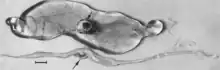

Figure 4. Embryos from a gilt experimentally infected oronasally immediately after breeding and killed 22 days later. Bar = 1 cm. (Top) Noninfected, clinically normal embryo (arrow) and associated extraembryonic membranes; (bottom) PPV-infected, dead littermate embryo (arrow) and associated extraembryonic membranes, recent death, no obvious resorption of soft tissues.[84]

Figure 5. Segment of uterus opened to show necrotic remnants of a partially resorbed PPV-infected embryo (arrows) and associated extraembryonic membranes of a gilt experimentally infected oronasally immediately after breeding and killed 22 days later; remnants are laden with virus and viral antigen. Bar = 1 cm.[84]